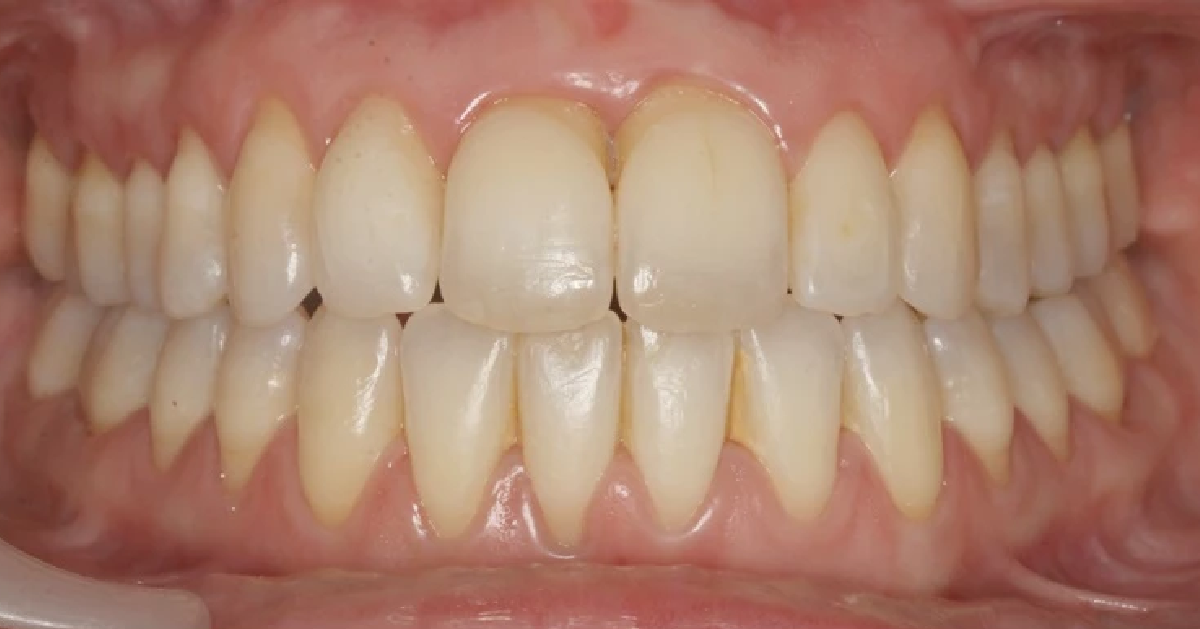

Vårt arbeid

Alle pasienter som vises har gitt skriftlig samtykke til at bildene kan brukes på klinikkens nettside.